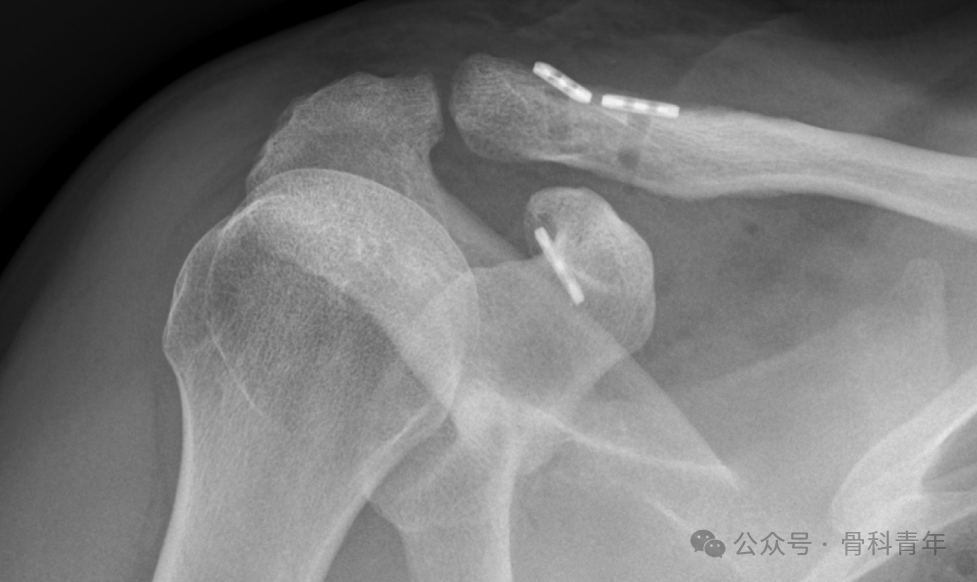

将锁骨纽扣沿其各自的FiberWire向自由端推进,以增加有效长度,便于后续操作。用电刀和骨剥部分分离斜方肌在锁骨止点,使用牵开器辅助显露。以肩锁关节为主要标志,在距关节2cm和4cm处放置导针,采用4mm钻头制备朝向喙突的锁骨隧道。使用Arthrex Banana-Lasso将锁骨纽扣通过隧道,注意避免牵拉蓝色缝线(用于最终收紧),防止纽扣旋转移位。

用骨剥压低锁骨,同时另一手以患肢为杠杆抬高肩部,实现肩锁关节临床复位。术者维持复位位置,助手逐步收紧双尾紧绳系统的缝线,无需严格打结,但为增强稳定性可进行缝合固定。术中通过透视检查确认复位效果,满意后剪断TigerWire(喙突侧)和白色缝线(锁骨侧),再打结并剪断蓝色缝线。